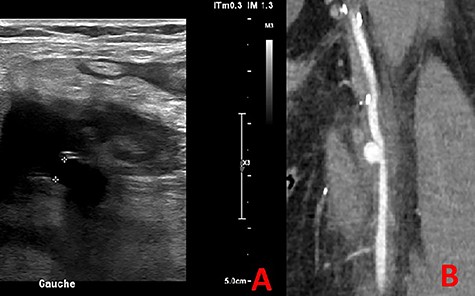

Ultrasonography (US) of the left thigh showed an aneurysmal dilatation of the SFA measuring 67 × 50 × 80 mm (Fig. 2) on the anterior aspect of the proximal third of the thigh. Computer tomography angiogram (CTA) confirmed a 64 × 80 × 87-mm PSA developed on the anterior side of the proximal left SFA (Fig. 3). The other arterial axes were healthy and normal. Supplementary imaging examinations did not identify any additional aneurysms.

Computer tomography angiogram showed a PSA of the proximal SFA.